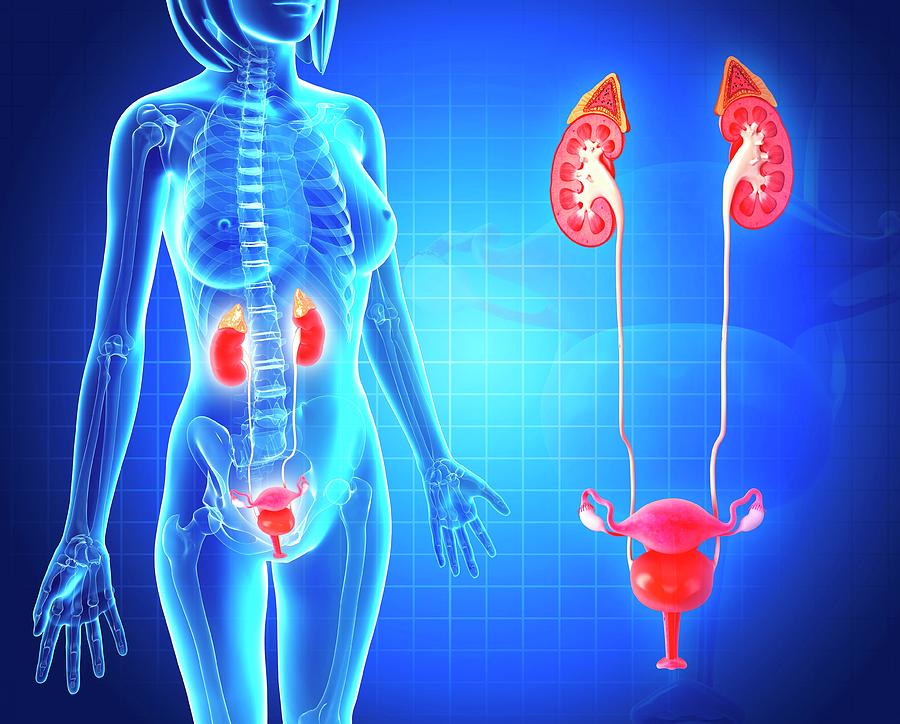

Natural treatments for kidney stones, infections, and other kidney-related issues.

Comprehensive Ayurvedic care for hormonal imbalances, menstrual problems, and more.